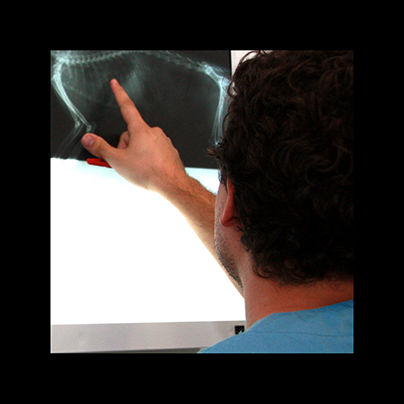

radiología

La radiologia es imprescindible en traumatologia y en algunos diagnosticos, ya sea mediante radiologia simple ó de contraste.

traumatología

En clinican podemos tratar las diversas afecciones que pudan afectar a huesos y articulaciones